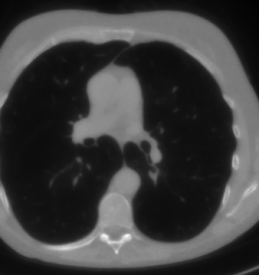

We now consider the P180,60subscript𝑃18060P_{180,60} CT protocol whose results are reported in Figure 6. In this case, the tomographic reconstruction is more challenging than in the previous experiment. The starting image xRISsubscript𝑥𝑅𝐼𝑆x_{RIS} has evident streaking artifacts and blur and some details are lost, especially in the first zoom. The artifacts are reduced in the xISsubscript𝑥𝐼𝑆x_{IS} (top right image), where some details are recovered and the edges are quite neat. The xINGsubscript𝑥𝐼𝑁𝐺x_{ING} image obtained with the proposed RISING (bottom right) is visually an excellent reconstruction. It is very similar to the xLPPsubscript𝑥𝐿𝑃𝑃x_{LPP} image, whose training, we remark, is based on more informative target images.

Figure 6: Results on a test image from the Mayo data set, under the P180,60subscript𝑃18060P_{180,60} CT protocol. Top-left: xRISsubscript𝑥𝑅𝐼𝑆x_{RIS}; top-right: xISsubscript𝑥𝐼𝑆x_{IS}; bottom-left: xLPPsubscript𝑥𝐿𝑃𝑃x_{LPP}; bottom-right: xINGsubscript𝑥𝐼𝑁𝐺x_{ING}.